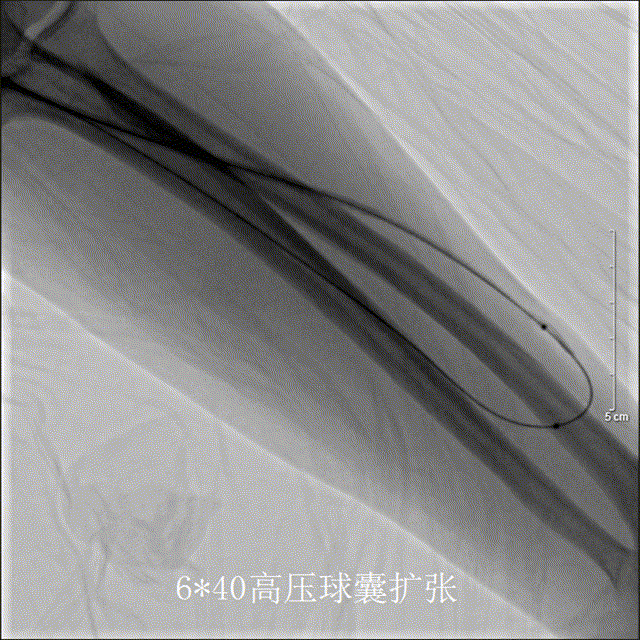

改用6*40mm高压球囊数次扩张狭窄段仍不能充分扩开

普通球囊及高压球囊扩张后,复查造影示内瘘血流较术前改善,但流出道狭窄段仍存在